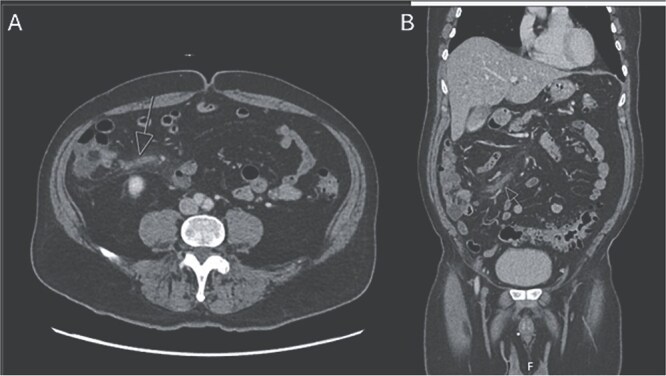

肠致病性大肠杆菌(EPEC)是大肠杆菌的一种致病性菌株。肠系膜静脉血栓性静脉炎是外科关注的问题,因为有肠缺血发展的风险。我们提出一个独特的情况下,病人与EPEC腹泻谁随后发展回肠结肠血栓性静脉炎。我们的病人以6天的腹泻和腹痛就诊于急诊科。腹部和骨盆计算机断层血管造影(CTA)显示回结肠静脉闭塞伴静脉周围炎症,符合肠系膜血栓性静脉炎。胃肠道聚合酶链反应(GI PCR)显示EPEC阳性。患者非手术治疗,静脉注射抗生素和抗凝治疗,症状消退。回结肠血栓性静脉炎是一种罕见的急性腹痛的原因。我们的病人是第一例在EPEC感染后发展为血栓性静脉炎的病例。我们假设EPEC感染和炎症使患者易患回肠结肠血栓性静脉炎。

Enteropathogenic Escherichia coli (EPEC) is a pathogenic strain of E. coli. Mesenteric vein thrombophlebitis is of surgical concern, as there is a risk of the development of bowel ischemia. We present a unique case of a patient with EPEC diarrhea who subsequently developed ileocolic thrombophlebitis. Our patient presented to the emergency department with 6 days of diarrhea and abdominal pain. A computed tomography angiography (CTA) abdomen and pelvis was performed which revealed occlusion of the ileocolic vein with perivenous inflammation, consistent with mesenteric thrombophlebitis. A gastrointestinal polymerase chain reaction (GI PCR) was positive for EPEC. The patient was managed non-operatively with intravenous antibiotics and anticoagulation with resolution of symptoms. Ileocolic thrombophlebitis is a rare cause of acute abdominal pain. Our patient is one of the first documented cases to develop thrombophlebitis following EPEC infection. We hypothesize the EPEC infection and inflammation predisposed our patient to developing ileocolic thrombophlebitis.